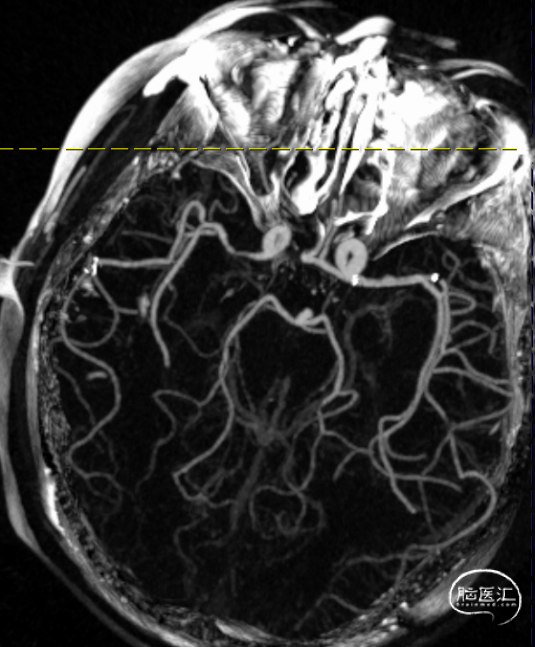

术前造影提示:左侧大脑中动脉闭塞,可见部分豆纹动脉显影,左侧大脑前动脉通过脑膜支代偿左侧大脑中上干。

0.014" 微导丝引导下支架微导管进入M2下干,保留导丝退回微导管,造影提示M2未见显影,考虑“首过效应”阴性。此时考虑病变性质狭窄基础上并大负荷血栓可能,不排除栓塞性病变可能。

沿微导管送入4.0*30mm Syphonet®取栓支架,造影显示:造影见左侧大脑中动脉M1段约1.8cm细长狭窄显影。大脑中动脉一干仍不显影,考虑狭窄明显并血栓形成。以静脉替罗非班推注12ml,同时静脉7ml/h维持。

沿4.0*30mm Syphonet®取栓支架输送导丝送入2.0*15mm SacSpeed®球囊扩张导管,于大脑中动脉狭窄段缓慢扩张成型后,保留Syphonet®取栓支架造影后提示远端血流改善。5分钟后支架锚定、负压下将6F Tethys®中间导引导管拟送至支架近端并接触血栓(中间导管无法到位),用50ml注射器保持抽吸管负压,回拉Syphonet®取栓支架,取出1枚2.0*2mm细小血栓。

取栓后复查造影见左侧大脑中动脉仍闭塞。

再次将4.0*30mm Syphonet®取栓支架释放到位并造影,见左侧大脑中动脉狭窄段仍明显,且靠近豆纹动脉处。